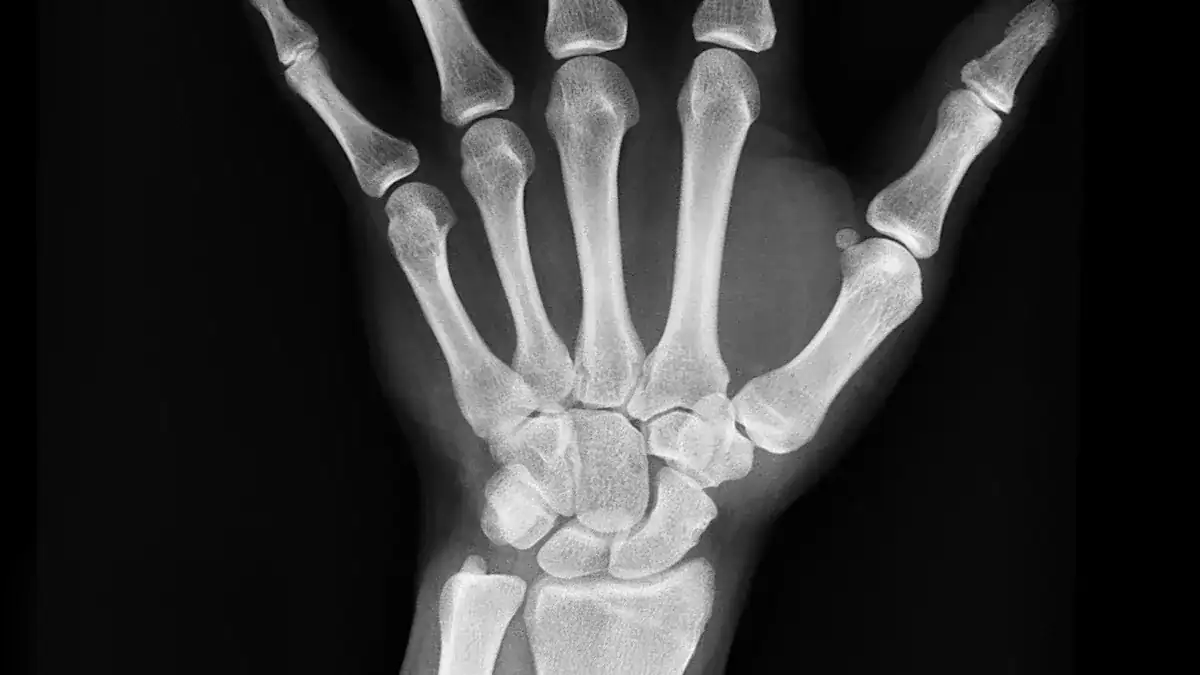

X-rays show your bones. They can reveal bone spurs or arthritis that might press on nerves.